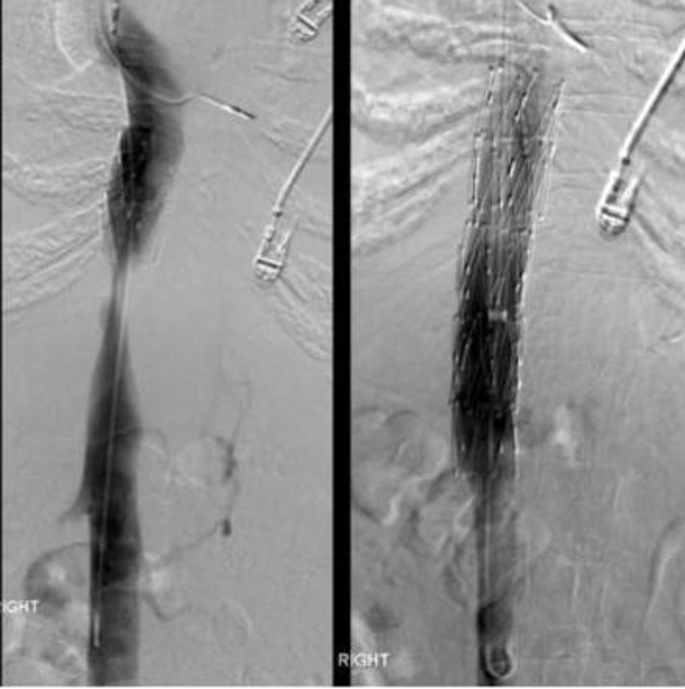

IVC stenosis and stent placement

the presence of venous collaterals indicates hemodynamically significant stenosis